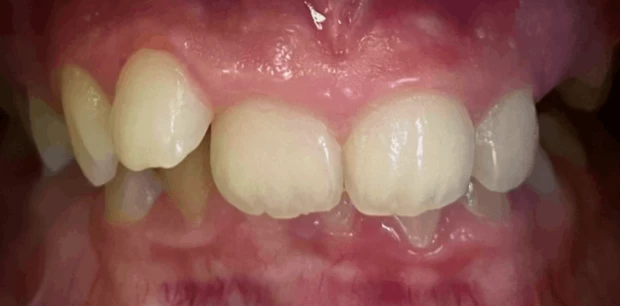

Ортодонтия

Исправление прикуса и выравнивание зубов брекет-системой

Пациент У., 15 лет. Родители обратились с жалобами на неровные зубы сына. Проведено ортодонтическое лечение брекет-системами. Лечение проводилось 2 года.